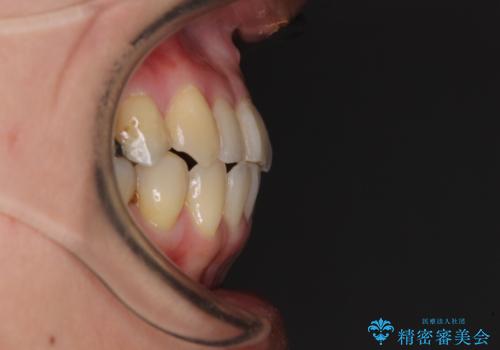

切端咬合をインビザライン矯正で解消

上下前歯の先端同士が接触する切端咬合であったため、上顎は歯列を拡大し、下顎はIPR(歯と歯の間を削る)により叢生を解消しながら歯列を小さくすることとしました。

切端咬合はスムーズに解消され、前歯の負担を軽減させることができました。